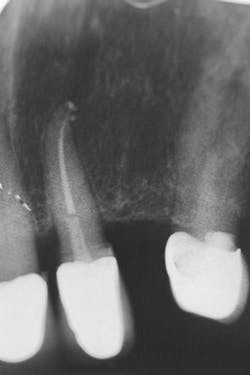

Figure 15: Final x-ray

A final x-ray was taken for records (figure 15). The post was homogeneously connected, ran between the existing root and the newly reattached PFM crown, and provided for a strong rebuild.